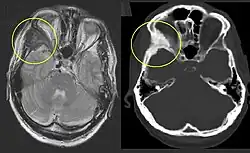

Die polyostotische FD ist klinisch und röntgenologisch auf den ersten Blick zu erkennen. Die befallenen Knochenbereiche weisen ein charakteristisches, milchglasartiges und unscharf begrenztes Erscheinungsbild im Röntgen oder CT auf. Eine Biopsie ist unnötig und erhöht die Bruchgefahr.

Bisphosphonate (Risedronate, Zoledronate) hemmen die Osteoklasten, behandeln aber wie die Operationen nicht die kausale Ursache der Erkrankung. Eingriffe am Achsskelett, wie Achskorrekturen und Stabilisierungen mit Marknägeln bergen einige Risiken. Bei Befall des Schädelknochens kann die Schutzfunktion desselben beeinträchtigt sein. Eine neurochirurgische Operation mit Exzision der Läsion im Gesunden und anschließender Rekonstruktion mit Kunstmaterialien (Titan oder Kunstmaterial wie PEEK, PMMA) kann entgegen den Eingriffen am Achsskelett ein risikoarmer und erfolgversprechender Therapieansatz sein.